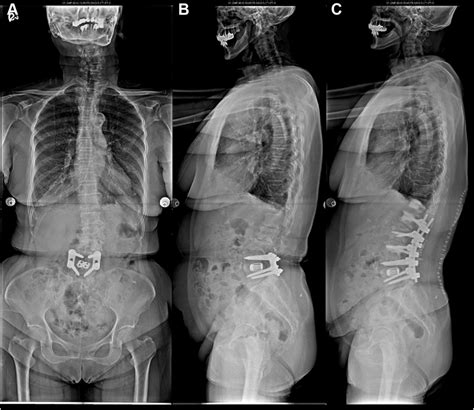

Alright, so how do doctors figure out if you have degenerative retrolisthesis of L1 on L2 ? The diagnostic process typically involves a combination of a physical exam, a review of your medical history, and imaging tests. First, your doctor will likely ask about your symptoms. They’ll want to know when the pain started, what makes it better or worse, and whether you’ve noticed any other symptoms like numbness or weakness. Next, they will perform a physical exam. This involves assessing your posture, range of motion, and reflexes. They may also check for tenderness in your lower back and perform tests to assess nerve function. Imaging tests play a crucial role in diagnosing retrolisthesis. X-rays are usually the first imaging test. They can reveal the slippage of the vertebra and help to rule out other causes of back pain. However, X-rays only show bones, not soft tissues like discs and ligaments. MRI (magnetic resonance imaging) is more detailed and often used to confirm the diagnosis. An MRI uses powerful magnets and radio waves to create detailed images of the spine, including the bones, discs, nerves, and soft tissues. It can show the extent of the slippage and whether any nerves are being compressed. A CT (computed tomography) scan might be used if an MRI is not possible or if the doctor wants a more detailed view of the bones. A CT scan uses X-rays to create cross-sectional images of the spine. The doctor might also order a bone scan to look for signs of arthritis or other bone abnormalities. Nerve conduction studies and electromyography (EMG) might be used if nerve compression is suspected. These tests measure the electrical activity of the nerves and muscles to assess nerve function. The results from all these tests help the doctor confirm the diagnosis of degenerative retrolisthesis of L1 on L2 and determine the best course of treatment. Accurate diagnosis is super important, because the treatment depends on the severity of the condition and the symptoms you are experiencing. So, if you’re experiencing back pain or other symptoms, don’t hesitate to see a doctor. Early diagnosis and treatment can often prevent the condition from getting worse.